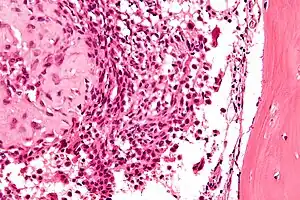

Pode ser localizado e medido com uma radiografia(RX), tomografia computadorizada (TC), ressonância magnética (MRI) ou cintilografia óssea, mas necessita uma biópsia para ser diferenciada de outros tumores ósseos. Exibem cartilagem imatura, células gigantes e edema medular assim como um fibroma condromixoide, mas geralmente podem ser diferenciados por sua localização. [3]